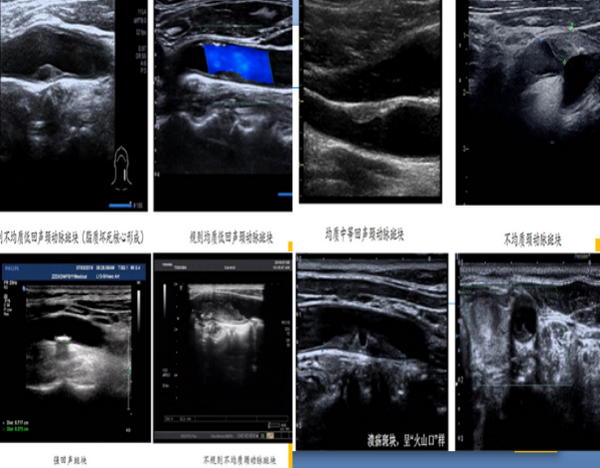

在日常工作中,颈动脉常规超声可以显示斑块的大小、位置、回声以及是否造成狭窄等。根据回声,将斑块分为低、中、高回声斑块,也就是以前常说的软斑和硬斑,大家通常认为硬斑就是稳定的,软斑就是不稳定的,其实这种解释是错误的。

不能简单的将回声作为评估斑块稳定性的标准。除外斑块回声、形态及纤维帽完整性,斑块内是否有新生血管也是评估斑块稳定性重要的依据,将斑块分为易损斑块和稳定斑块两种,早期识别易损斑块并进行有效干预,有助于脑卒中的预防。